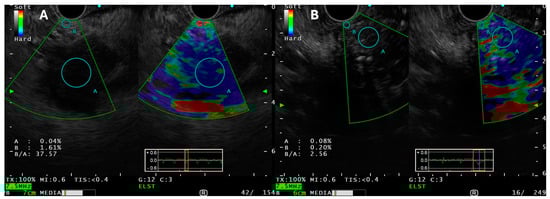

3.4.5. Data on Use of EUS-E Versus Standard EUS-FNA/B for Pancreatic Tissue Sampling